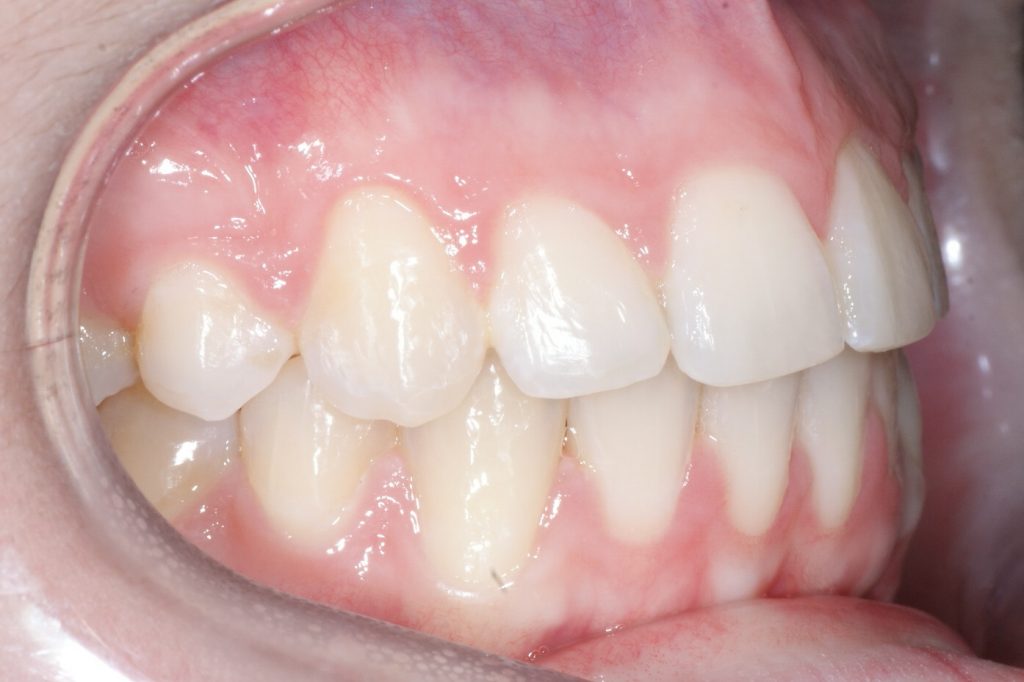

Correction d’une malocclusion de type Classe II division 1, surplomb horizontal inadéquat et chevauchement modéré aux 2 arcades. Des appareils fixes (broches et vis d’expansion) et des élastiques furent nécessaires pour améliorer ce sourire. Traitement chez une adolescente, réalisé en 18 mois.